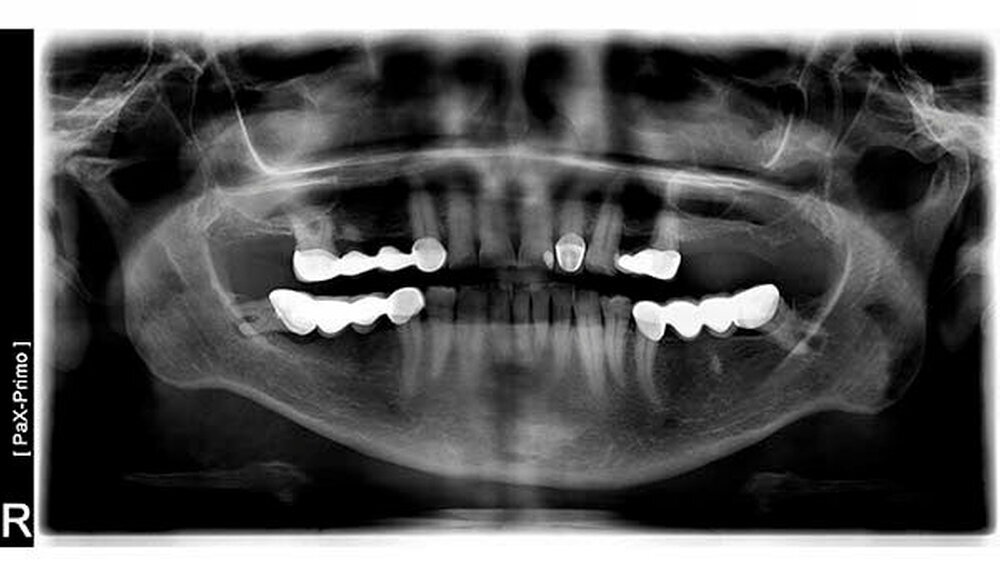

"Hier das Röntgenbild einer 13 Jahre alten russischen Brücke. Die Patientin war heute aufgrund von starken Zahnschmerzen zur Kontrolle zum ersten mal in unserer Praxis vorstellig. Weder wir noch unser Zahntechniker können sich erklären, wie diese Brücke einzementiert werden konnte. Ebenso ist uns schleierhaft, wie der untere (dem Zahnfleisch zugewandte )Teil des Zahn beschliffen werden konnte. Die Brücke weist kein Geschiebe auf. Der Zahn 48 ist natürlich nicht mehr erhaltungswürdig. Vielleicht hat ein Leser eine Antwort?"Dieser Beitrag wurde eingereicht von Dr. Dan-Liviu Tite und Dr.-medic stom. Vivian-Zeno Tite, Augsburgerstr.13, in 86368 Gersthofen